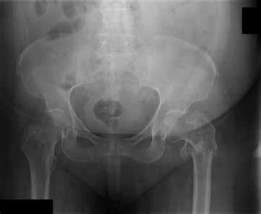

Q. 1Figure 1 is the radiograph of a 62-year-old woman who fell and sustained a left hip fracture. A radiographis shown in Figure 1. Which of the following preoperative risk factors is associated with the highest postoperative mortality rate?